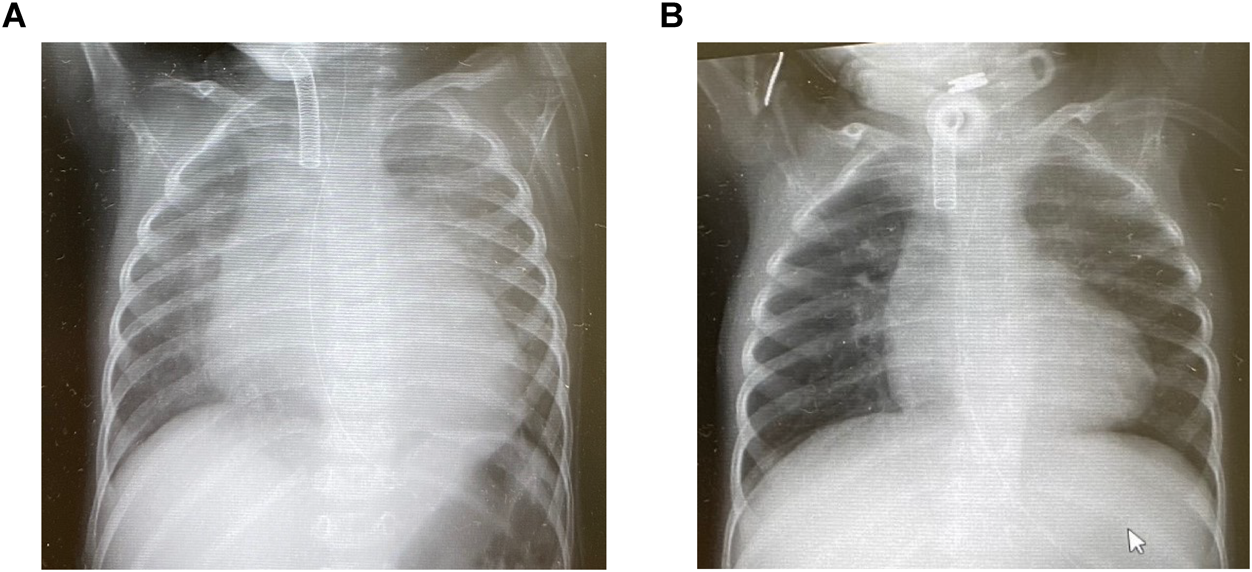

心筋緻密化障害の2歳男児.心収縮性の低下により,うっ血性心不全に至った症例である.末梢血中ナトリウム利尿ペプチドは上昇(7,879 pg/mL)し,胸部レントゲン写真では心拡大と肺うっ血像を認めた(Fig. 6A).心拍数は130/分,末梢血圧は90/40 mmHg,超音波検査では左室拡張末期径35 mm(正常値の135%),容積換算でおよそ正常値の200%,駆出分画(Simpson)30%であった.フロセミド/アルダクトン2 mg/kg/day,マレイン酸エナラプリル0.2 mg/kg/day,カルベジロール0.4 mg/kg/dayを内服していたが,心拡大進行し,管理を検討することとなった.

Fig. 6 Chest X-ray images before (left) and after (right) treatment

A patient with dilated cardiomyopathy, who was refractory to medications including diuretics, enalapril and carvedilol, was treated with digoxin, pimobendane and water restriction based on the concept of the pressure–volume relationship. Reverse remodeling, of which there was much more than expected, was introduced, as shown in the chest X-ray.

これらによって,全身状態が改善し,在宅管理が可能となった.次の段階として,心筋のリバース・リモデリングが見込めないかと考えた.心筋酸素消費はESPVR, EDPVRおよび心室圧容積ループで囲まれた面積に正相関する7)ことが知られている.心筋収縮改善に伴い,心筋酸素消費は増加に転じるため,ヘモグロビン値12 g/dLを下限として輸血をためらわないこと,拡張末期圧上昇は冠血流増悪に関わることから体重を連日自宅で測定する水分管理を導入した.幸運なことに約半年の経過でリバース・リモデリングを導入することができ,BNPは11 pg/mLまで低下した.この症例では,心拡大は改善したが,依然少量の水分負荷で浮腫増悪をきたすことから,感染症・貧血に注意しつつ脱水気味のバランスで慎重に管理を継続している(Fig. 6B).